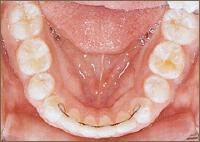

Die erste Zahnspange

Falls notwendig, werden neue Abdrücke genommen, um ein Gerät anfertigen zu können, oder es wird schon ein neues Gerät eingesetzt.

Ab jetzt spricht man von einer laufenden Behandlung. Alle 4-6 Wochen (je nach Gerät und Entwicklungsstadium) finden Kontrolltermine in der Praxis statt, um die Wirkung der Geräte zu überprüfen.